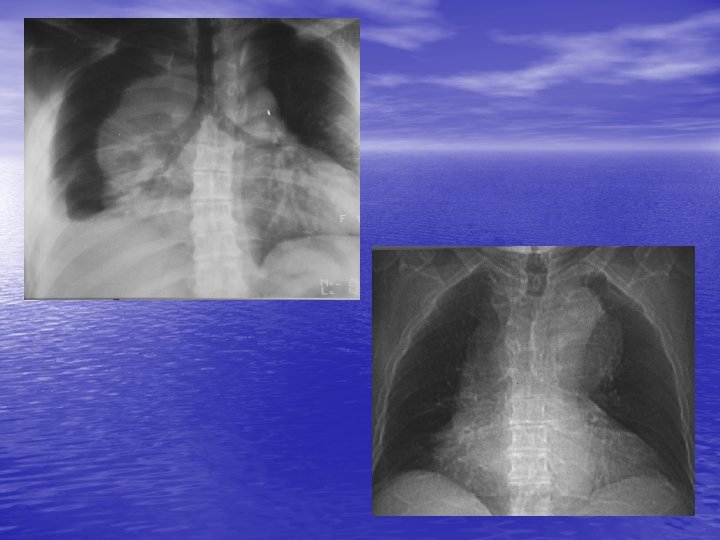

2. TECHNIQUES D’IMAGERIE 2. 1. Radiographie thoracique - Modification des lignes médiastinales. - 3 compartiments : antérieur (en avant de la ligne face antérieure de la trachée-bord postérieur du cœur), moyen (en avant de la ligne passant 1 cm en avant des corps vertébraux), postérieur. - Division verticale supérieure (au-dessus du bord supérieur de l’aorte horizontale), moyen (audessous du plan de la carène), inférieur.

3. MASSES DU MEDIASTIN ANTERIEUR 3. 1. Tumeurs thymiques - Environ 50 % des masses non ganglionnaires et vasculaires. - Tumeurs les plus fréquentes du médiastin antérieur. - 50 % asymptomatiques, myasthénie. - Bénin ou malin : souvent pas de différenciation par l’imagerie.

3. 2. Autres tumeurs - Tumeurs germinales (tératome, carcinome embryonnaire). - Adénome parathyroïdien. - Lymphangiome kystique. - Kyste pleuro-péricardique. - Goitre plongeant. - Pseudo tumeur graisseuse (par hernie diaphragmatique antérieure), vasculaire (anévrysme de l’aorte ascendante ++), cardiaque.